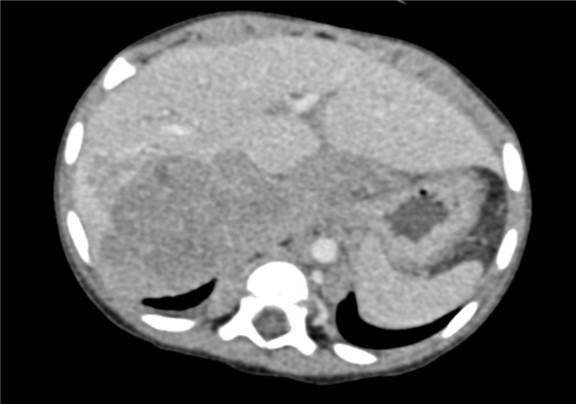

下腹部增强CT示:右肾上腺区占位并周围侵犯,腹腔、腹膜后多发淋巴结肿大,考虑恶性肿瘤,神经母细胞瘤?胆囊炎可能性大。

术前CT检查:

动脉期